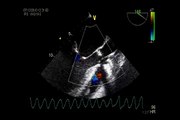

Cardiac arrest VENTRICULAR FIBRILLATION DURING TOE